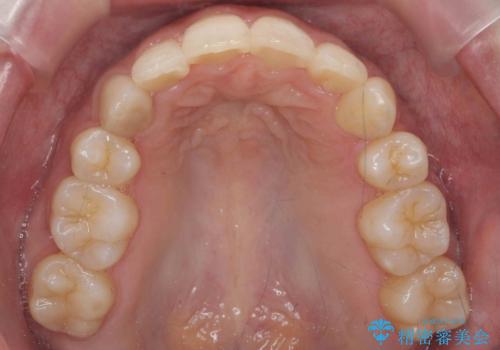

下顎がとても小さく後方位であるため、オトガイの閉口時のシワは完全になくすことは難しかったですが、前歯も大きく下がり満足していただきました。

矯正治療は審美的な側面を持っておりますが、小さすぎる下の顎に口元を無理やりあわせるのも、歯の移動量が大きすぎて適切な治療とは言えないと思います。健康を損なう美容整形とは違うからです。前歯については、適度に下げる量をコントロールすることも大事です。